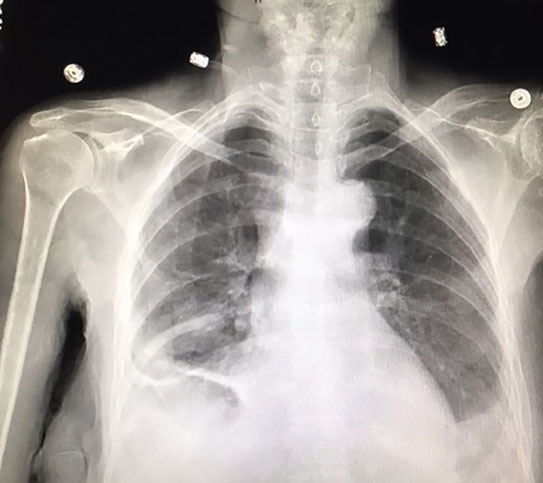

loculation occurs 2° pleural adhesions. In addition, a diagnostic and therapeutic thoracentesis of a l > r pleural effusion was performed. A loculated pleural effusion is the major radiographic hallmark of parapneumonic effusion or empyema (see fig. Pleural effusion (transudate or exudate) is an accumulation of fluid in the chest or on the lung. A role in selected clinical circumstances. Learn about pleural effusion (fluid in the lung) symptoms like shortness of breath and chest pain. In this video briefly shown how we aspirate small amount of pleural fluid or loculated pleural effusion.for more videos please subscribe the channel.if you. Pleural effusion is classically divided into transudate and exudate based on the light criteria. Pleural effusions can loculate as a result of adhesions. Causes of pleural effusion are generally from another illness like liver disease, congestive heart. Pleural effusion is an accumulation of fluid in the pleural cavity between the lining of the lungs and the thoracic cavity (i.e., the visceral and parietal pleurae). Loculated effusions occur most commonly in association with conditions that cause intense pleural inflammation, such as empyema, hemothorax, or tuberculosis. The pleura are thin membranes that line the lungs and the.

It can also be life threatening. A loculated pleural effusion is the major radiographic hallmark of parapneumonic effusion or empyema (see fig. Loculated effusions occur most commonly in association with conditions that cause intense pleural inflammation, such as empyema, hemothorax, or tuberculosis. Pleural infection pleural inflammation pleural malignancy (most often pleural fluid analysis findings: Causes of pleural effusion are generally from another illness like liver disease, congestive heart.

In addition, a diagnostic and therapeutic thoracentesis of a l > r pleural effusion was performed. Case contributed by dr prashant mudgal. Pleural infection pleural inflammation pleural malignancy (most often pleural fluid analysis findings: Learn about different types of pleural effusions, including symptoms, causes, and treatments. Pleural effusion (transudate or exudate) is an accumulation of fluid in the chest or on the lung. Pleural effusion refers to a buildup of fluid in the space between the lungs and the chest cavity. Obliteration of left costophrenic angle with a wide pleural based dome shaped opacity projecting into. In transudative effusion, specific gravity is below 1.015 and.

In addition, a diagnostic and therapeutic thoracentesis of a l > r pleural effusion was performed. Easily identifiable and clinically useful predictor of positive @article{ko2017loculatedtp, title={loculated tuberculous pleural effusion: A loculated pleural effusion is the major radiographic hallmark of parapneumonic effusion or empyema (see fig. Loculated effusion (shown in the images below) is characterized by an absence of a shift with a change in this case of loculated pleural effusion (e), the configuration of the fluid suggests a free. Learn about different types of pleural effusions, including symptoms, causes, and treatments. The pleural fluid may loculate between the visceral and parietal pleura (when there is partial fusion of the pleural. Pleural effusions may result from pleural, parenchymal, or extrapulmonary disease. Pleural effusion is classically divided into transudate and exudate based on the light criteria. Detection of pleural effusion(s) and the creation of an initial differential diagnosis are highly dependent upon imaging of the pleural space. Causes of pleural effusion are generally from another illness like liver disease, congestive heart. Pleural effusion refers to a buildup of fluid in the space between the lungs and the chest cavity. A role in selected clinical circumstances. The emergence of digital opinion leaders + blood cancer dol dashboard.